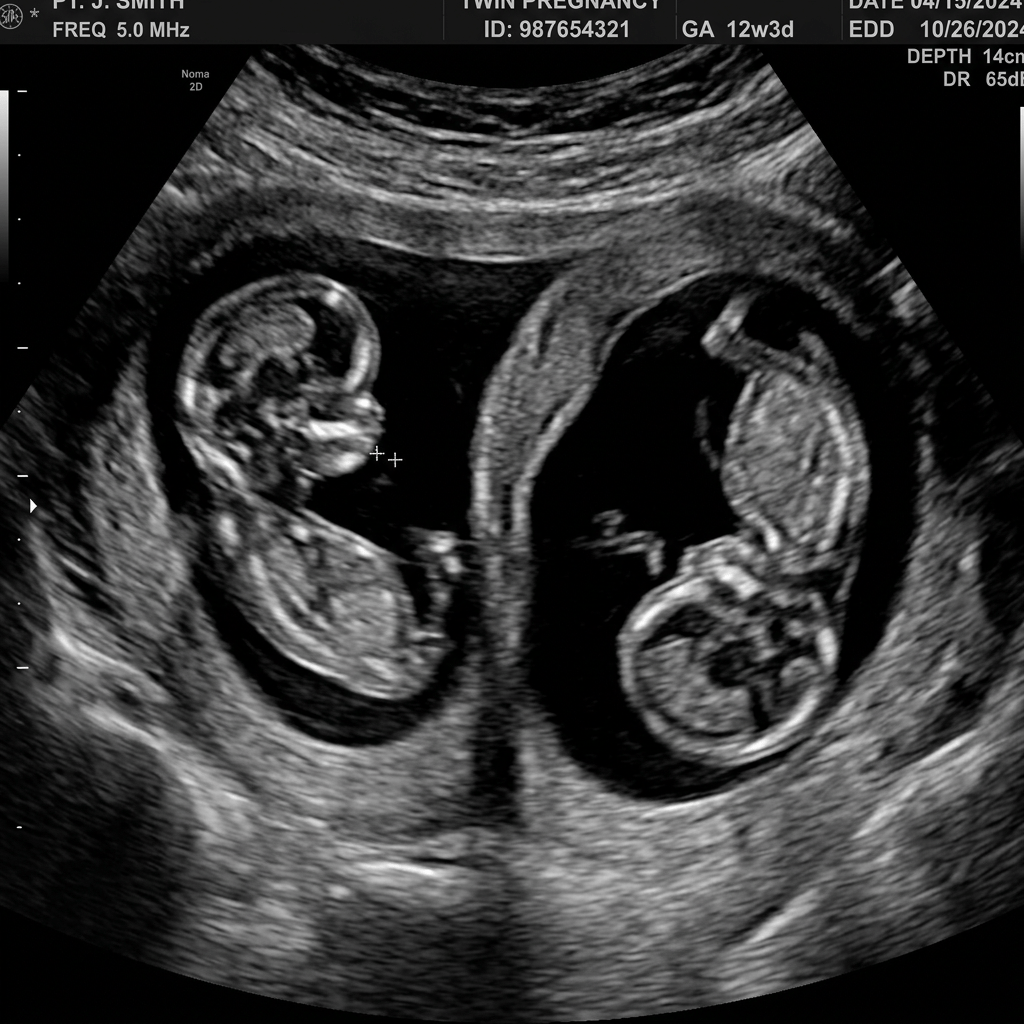

Dubbel geluk, dubbel verlies, ondraaglijke leegte

In deze blog neem ik je mee naar de bevalling van Nina en Thomas. Zij verwachtten hun eeneiige tweeling die ze nooit levend in hun armen hebben mogen sluiten. Tegelijkertijd begeleidde ik de geboorte van een gezonde vierde baby voor een andere moeder. Het verhaal laat zien hoe kwetsbaarheid, verdriet, trots en blijdschap in mijn vak constant naast elkaar bestaan en hoe waardevol het is om gezinnen in zulke momenten bij te staan.